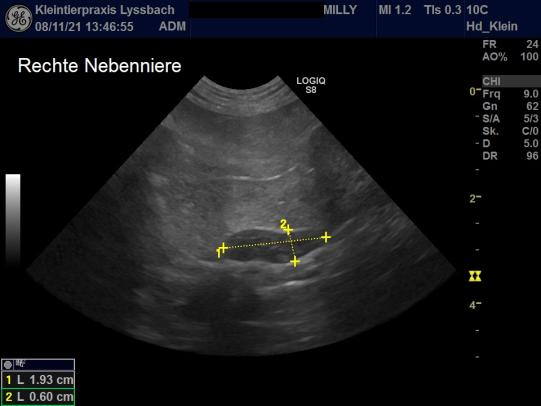

Die Vorgeschichte (Gangprobleme, erhöhte Trinkmenge, eingeschränkte Sehkraft) und die Untersuchungsergebnisse (Hautveränderungen und Hautqualität, neurologische Defizite, erhöhter Blutzucker) wecken den Verdacht, dass Milly an einer bei Katzen seltenen Nebennierenüberfunktion leiden könnte. Zum Beweis der Erkrankung müssen weitere Bluttests (Dexamethason-Hemmtest) und eine CT- oder MRT-Aufnahme durchgeführt werden; allerdings kann auch eine Ultraschalluntersuchung wertvolle Hinweise liefern. Tatsächlich ist im Ultraschall ersichtlich, dass beide Nebennieren von Milly stark vergrössert sind: Normalerweise ist dieses Organ bei der Katze etwa 11 Millimeter lang und 4.3 mm dick; bei Milly sind die Nebennieren mit ca. 19 mm x 6 mm viel grösser. Mit sehr hoher Wahrscheinlichkeit leidet die Katze an einer Nebennierenüberfunktion (Hyperadrenocorticismus) und parallel verlaufender Zuckerkrankheit (Diabetes Mellitus).